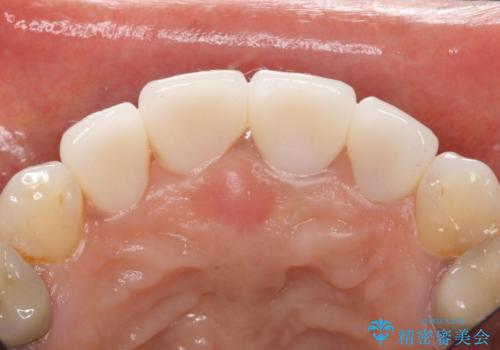

5年前のクラウン装着時と比較したところ、歯肉が成熟し歯間乳頭ができており、より天然歯のように自然に見えました。

患者様の良好なセルフケアと精密な適合の良いクラウンにより、歯肉の腫脹や退縮も認められませんでした。

人工のダイヤモンドにも用いられるジルコニアは、セラミック系素材の中でも圧倒的に丈夫かつ審美的で、劣化しにくく口腔内でも長期間安定した状態を保つことができます。

クラウンの種類:ジルコニアオールセラミッククラウン スタンダード